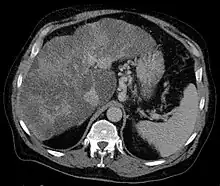

Gastric varices are dilated submucosal veins in the lining of the stomach, which can be a life-threatening cause of bleeding in the upper gastrointestinal tract. They are most commonly found in patients with portal hypertension, or elevated pressure in the portal vein system, which may be a complication of cirrhosis. Gastric varices may also be found in patients with thrombosis of the splenic vein, into which the short gastric veins that drain the fundus of the stomach flow. The latter may be a complication of acute pancreatitis, pancreatic cancer, or other abdominal tumours, as well as hepatitis C. Gastric varices and associated bleeding are a potential complication of schistosomiasis resulting from portal hypertension.

Secondly, patients with acute pancreatitis may present with gastric varices as a complication of a blood clot in the splenic vein. The splenic vein sits over the pancreas anatomically, and inflammation or cancers of the pancreas may result in a blood clot forming in the splenic vein. As the short gastric veins of the fundus of the stomach drain into the splenic vein, thrombosis of the splenic vein will result in increased pressure and engorgement of the short veins, leading to varices in the fundus of the stomach.